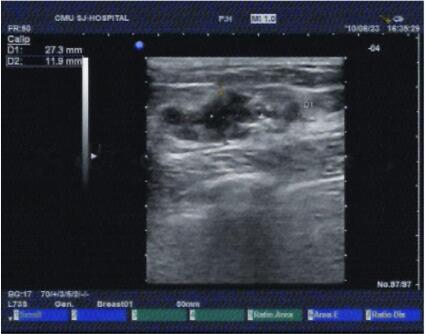

图2 乳腺三维超声检查:双乳腺体回声粗糙,左乳腺外上象限可见2.7cm×1.2cm肿物,形态不规整,边界模糊,CDFI可检出较丰富血流信号。诊断为左乳腺肿物,乳腺癌可能性大(BI-RADS:5类)